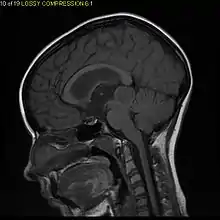

Diagnostic method | MRI, CT scan |

Usually – depending on the interview of the patient and after a clinical exam which includes a neurological exam and an ophthalmological exam – a CT scan and/or an MRI scan will be performed to confirm the presence of a tumor. They are usually easily distinguishable from normal brain structures using these imaging techniques. A special dye may be injected into a vein before these scans to provide contrast and make tumors easier to identify. Pilocytic astrocytomas are typically clearly visible on such scans, but it is often difficult to say based on imaging alone what type of tumor is present.